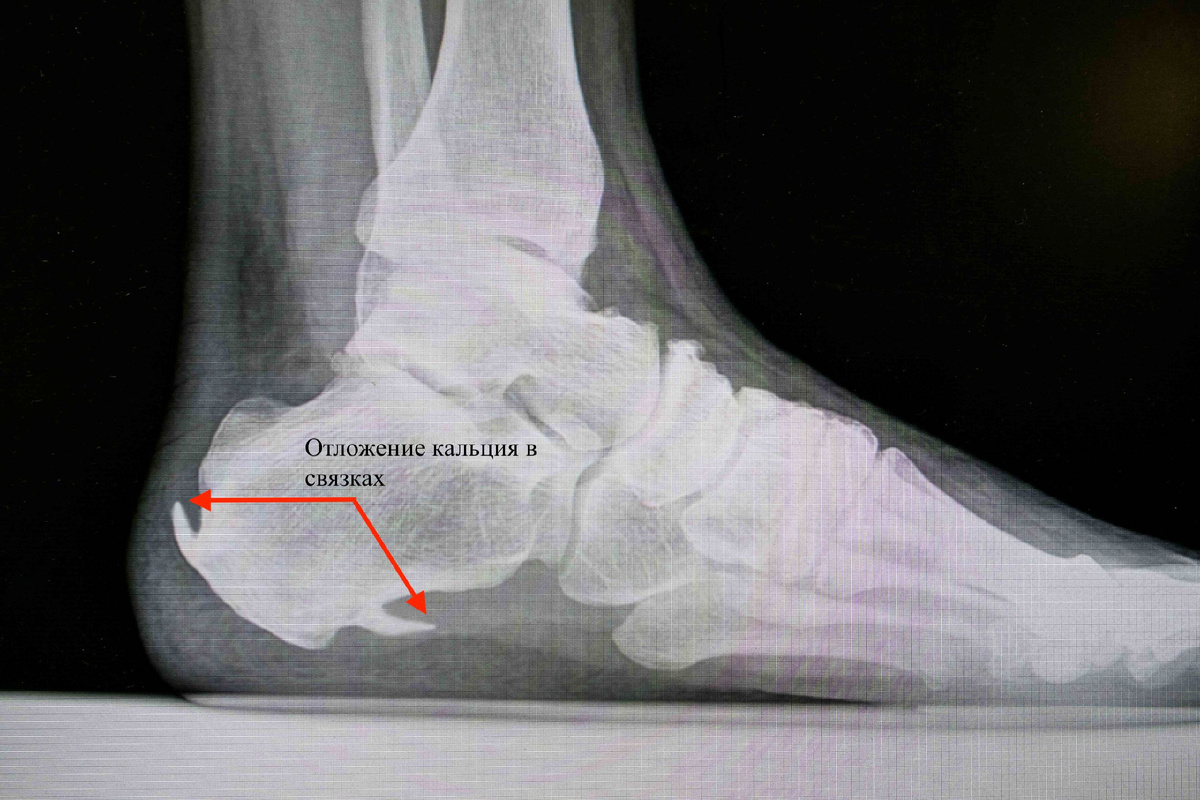

Название шпоры эта болезнь получила в эпоху когда из методов диагностики был только рентген, на котором виден костный вырост пяточной кости. Долгое время (некоторые и сейчас) думают, что виной всему является эта шпора и ее нужно разбить или растворить с помощью лечения.

На самом деле обызвествление связок стопы возникает в связи с большой нагрузкой на стопу, и организм приспосабливаясь к ней, откладывает кальций, поэтому никаких солей выводить из организма не нужно.